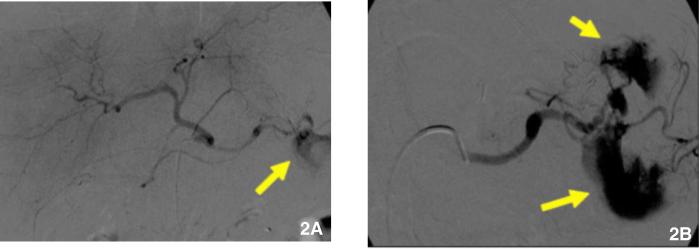

Hemosuccus pancreaticus is a rare cause of gastrointestinal bleeding from the duct of Wirsung into the duodenum via the ampulla of Vater. Hemosuccus pancreaticus is difficult to diagnose because the bleeding is usually intermittent, and the clinical findings are often discordant. Patients present with pain, either left upper quadrant or epigastric, and bleeding, which may present as melena, bright red blood per rectum, or even shock, if the hemorrhage is severe. Hemosuccus pancreaticus is usually caused by rupture of a pseudoaneurysm of a peri-pancreatic artery, often the splenic artery, in the setting of pancreatitis; other causes are very rare. In this report, for the first time to our knowledge, we present a case of hemosuccus pancreaticus that occurred as a complication of bariatric surgery.

胰源性腹水是一种罕见的导致胃肠道出血的病因,其出血途径为胰管经十二指肠乳头进入十二指肠。胰源性腹水难以诊断,因为出血通常是间歇性的,且临床症状往往不一致。患者表现为左上腹或上腹部疼痛以及出血,出血可能表现为黑便、直肠鲜红色血便,若出血严重甚至会出现休克。胰源性腹水通常由胰腺炎时胰周动脉(常为脾动脉)假性动脉瘤破裂引起;其他病因非常罕见。据我们所知,在本报告中,我们首次呈现了一例作为减肥手术并发症出现的胰源性腹水病例。